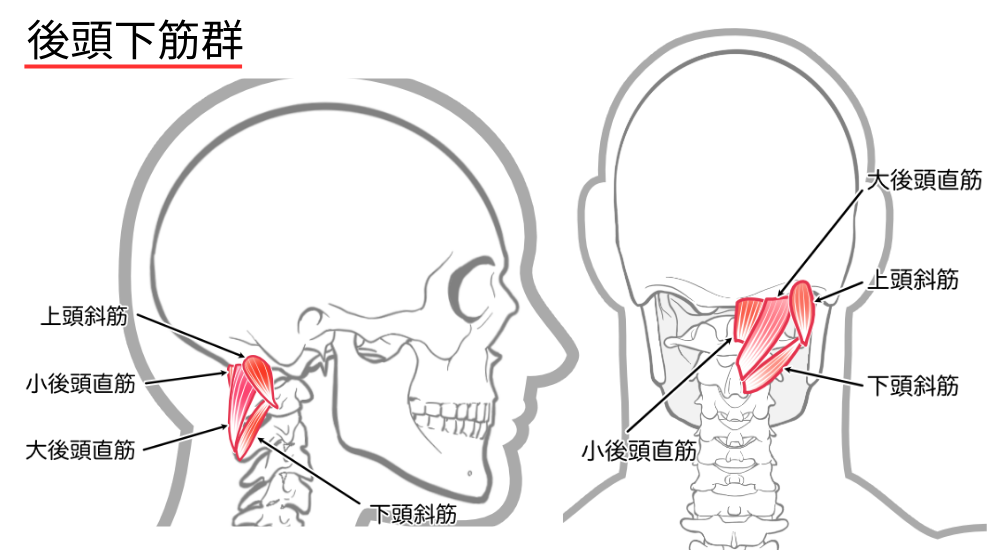

- 後頭下筋群: 後頭部と首の付け根の深層筋。ストレートネックや眼精疲労で緊張し、頭痛の原因となります。